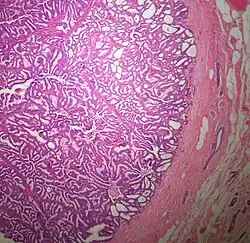

Papillary ductal carcinoma in situ

The microscopic histopathology of typical PDCIS lesions (refer to adjacent high-power photomicrograph) prepared with a hematoxylin and eosin stain consists of mammary ducts that have papillary fronds (i.e. thin, finger-like or leaf-like structures) lined with one or several layers of neoplastic, columnar-shaped epithelial cells (i.e. tall, narrow cells with their nuclei close to the site of their ductal attachment).[4] The fronds have branching fibrovascular cores. Epithelial cells lining the fronds' inner surfaces commonly form solid, cribriform (i.e. large nests of cells perforated by many rounded, variably sized spaces), or micro-papillary patterns. There may be a second population of epithelial cells lining the papillae that have abundant clear cytoplasm in addition to the usual neoplastic epithelial cells which line the papillae. These cells, which are not myoepithelial cells, have been termed globoid cells.[7] They have eosinophilic cytoplasm (i.e. pink or red cytoplasm due to its uptake of eosin stain).[6] PDCIS tumors with these cells have been termed dimorphic variants of PDCIS.[3] Myoepithelial cells are typically present at the periphery of the fronds but absent within the involved ducts.[4][7] The presence of a fibrous capsule and/or absence of peripherally located myoepithelial cells are strong indicators that the tumor is an ESP rather than a PDCIS.[3] PDCIS tissues may also contain areas of "Comedo-type necrosis", i.e. areas where dead cells have accumulated.[6]